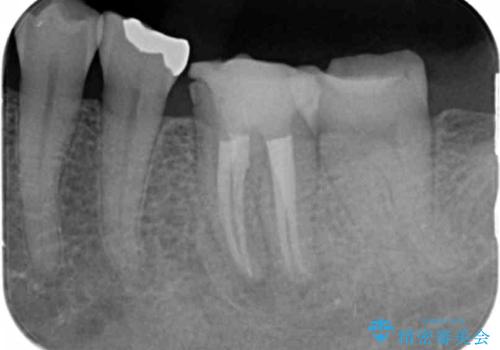

X線写真より根の先に病変が認められたため、根管治療を行ったのちジルコニアクラウンによる咬合機能回復治療を計画します。

根管治療を行ったのち、噛んだときに生じていた痛みも改善し、またしっかりと噛んで食事ができるようになりました。